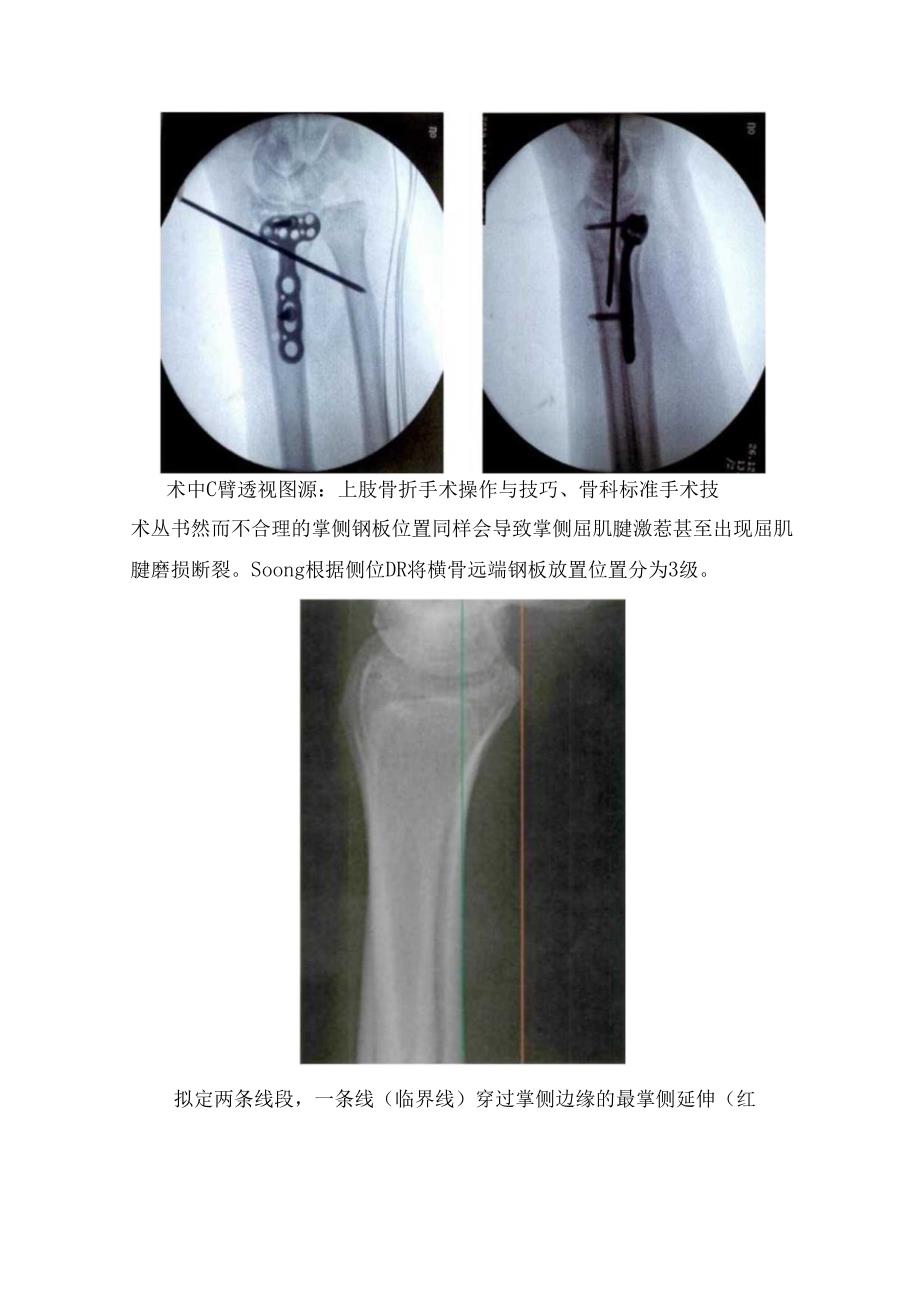

1、临床槎骨远端骨折掌侧入路要点掌侧Henry入路放置钢板是治疗横骨远端骨折的一种普遍术式。虽然较背侧入路复杂,但术后对伸肌腱影响较小,同时可以兼顾税侧柱、中间柱,避免分离横骨远端背侧1.iSter结节。改良Henry入路,沿横侧腕屈肌可触及肌腱行直皮切口,必要时可延长。显露税侧腕屈肌于槎侧腕屈肌与梳动脉间隙分离,牵开梳侧腕屈肌显露旋前方肌,并于槎侧缘离断。牵开旋前方,显露槎骨掌侧面,并安放钢板术中C臂透视图源:上肢骨折手术操作与技巧、骨科标准手术技术丛书然而不合理的掌侧钢板位置同样会导致掌侧屈肌腱激惹甚至出现屈肌腱磨损断裂。Soong根据侧位DR将横骨远端钢板放置位置分为3级。拟定两条线段,一条

2、线(临界线)穿过掌侧边缘的最掌侧延伸(红线),另一条平行于横骨轴的掌侧皮质骨(绿线),判定钢板是否突出,对屈肌腱造成激惹。红线:侧位经税骨远端最远端凸起的垂线;蓝线:经槎骨远端掌侧皮质的垂线。图A:O级,接骨板位于红线内;图B:1级,接骨板接触红线,但仍位于掌侧皮质近端;图C:2级,接骨板位于掌侧皮质远端。1、2级钢板板位置更容易造成更多的肌腱激惹,同时并建议钢板放置在O级标准位置,或使用低切迹钢板。因此,引入税骨掌侧“分水岭”这一概念,即横骨远端掌侧理论上最凸起的一条线。远端楮骨模型的前侧和外侧照片,箭头所示即楼骨掌侧“分水岭”。在尺侧半,存在黄色和蓝色两条凸起线,在横侧只有绿色一条凸起线。红色线为旋前方肌的止点线。因此,分水岭应该为尺侧半蓝色线与槎侧半绿色线的连线。分水岭线(WS)即为“划定横骨掌侧缘最掌侧的理论线”,作为掌侧钢板的远侧缘,以最小化屈肌腱损伤。PQ:旋前方肌水平线;VR:横骨掌侧放射状脊;WS:分水岭线;X:掌侧放射状结节;模骨远端骨折掌侧入路: